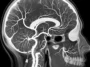

in BrainsBrain Angiography: Understanding Life-Saving Diagnostic Procedure